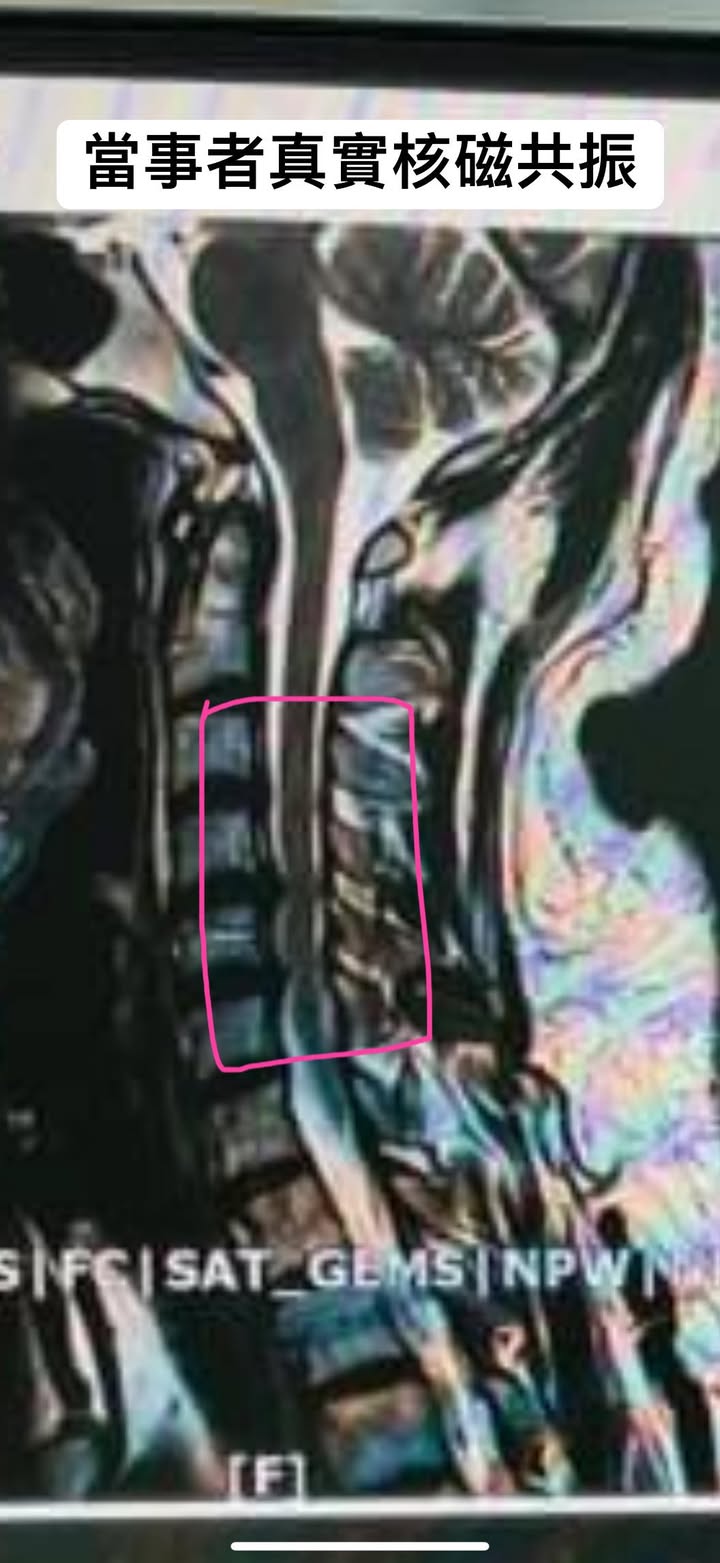

🔹這個患者年紀還不到40歲,最主要會發生這個問題是之前有個外傷將近快七八年前出一場車禍,從那一次就種下一個禍根,到診所的時候除了上半身肩膀的酸痛還有合併咽喉異物感比較奇怪的是患者都不知道為什麼他的雙腳會發軟,去做過腰椎的檢查也都沒事,但是因為當初都沒有拍到最新的核磁共振,結果我們才發現他的頸椎第四第五第六節後縱韌帶已經鈣化!

MRI上由於後縱韌帶變厚,脊髓受到了由前向後的壓迫,導致脊髓的壓縮變形,在這個漸進的慢性病程中,如果壓迫損傷加重則可能出現脊髓壞死加重或脊髓軟化病變。